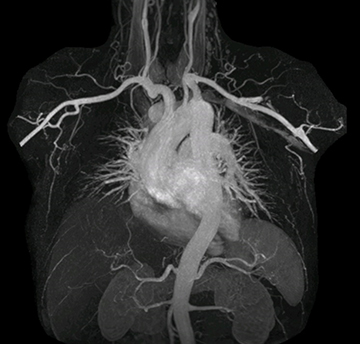

MRA run-off study with mDIXON

The subtractionless peripheral MR angiography shows improved vessel-to-background contrast and high resolution. Ingenia Ambition 1.5T.

Station

Ingenia Ambition

Pelvis

Voxels 1.3 x 1.3 x 3.2 mm, FOV 430 mm, 125 slices

Upper legs

Lower legs

Voxels 1.0 x 0.82 x 2.0 mm, FOV 430 mm, 125 slices

Subtractionless MRA run-off studies with exceptional spatial and temporal resolution

“In our peripheral MRA run-off studies with Ambition we realize key benefits, including outstanding image quality and significantly reduced breath-hold and scan times, which not only benefit the patient, but also provide the opportunity to add sequences that could aid in diagnosis,” Dr. Peña says.

“Before we had Ingenia Ambition, our CE-MRA run-off studies would first acquire a dynamic pre-contrast scan with 20-25-second breath-holds, then inject the contrast, do another acquisition and then subtract the two,” says Avila. “Now, mDIXON XD allows us to complete the study in just one single pass – without need for a pre-exam – which eliminates subtraction artifacts and almost halves the scan time. In addition, mDIXON provides much better background suppression, which really improves vesselto-background contrast. And, thanks to Compressed SENSE, the single breath-hold is not long and we improve image resolution.”